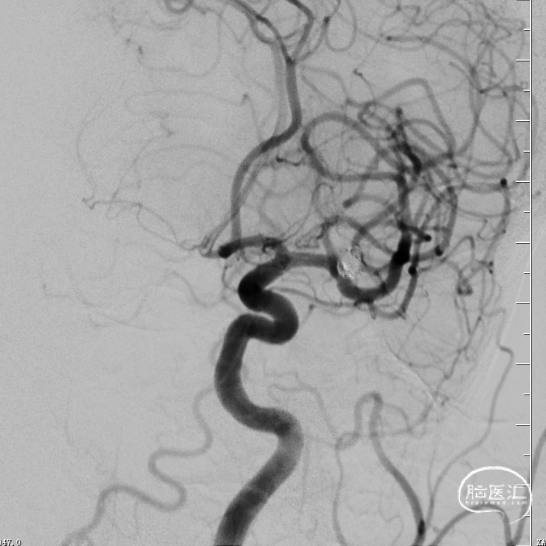

引入8F 导引导管及6F 中间导管至左侧颈内动脉,接加压管肝素盐水(500ml盐水2000单位肝素)4路;200cm Synchro-14微导丝配合SL-10微导管超选进入左侧大脑中动脉M1段上干备用(大脑中动脉M1段上干与动脉瘤瘤颈关系密切);200cm Synchro-14 微导丝配合Echelon-10微导管超选进入瘤体内,沿微导管填入Target 3mm×10cm 3D弹簧圈一枚成篮良好;后经SL-10微导管送入Atlas 3.0mm×24mm支架直至支架中部位于瘤颈处,缓慢释放支架,释放支架时通过半释放状态在瘤颈部小心推压将支架形成“穹窿”,穹顶部分支架可疝入瘤颈处,将宽颈动脉瘤变为窄颈。造影示支架稳定、帖壁良好;继续沿微导管行动脉瘤内弹簧圈栓塞术,先后放入2mm×6cm(两枚)、2mm×4cm、2mm×4cm、1.5mm×2cm弹簧圈共6枚;

释放支架前经导引导管缓慢注入替罗非班6ml,之后持续静脉泵入,速度5ml/h。手术历时60分钟,麻醉顺利苏醒,神经系统查体:未见阳性体征。NIHSS评分:0分;Raymond分级:Ⅰ级,mRS评分:0分。术后即刻行C-arm CT头颅扫描,未见出血,动脉瘤填塞致密,支架开放良好。